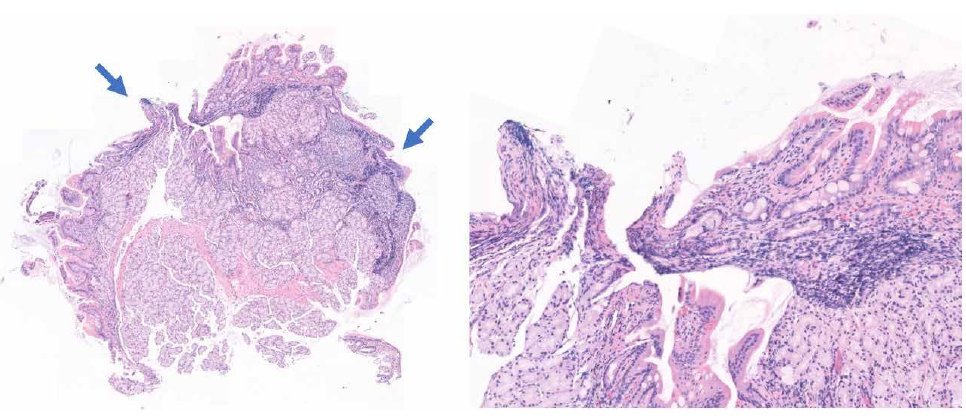

Figuur 1. Duodenumbiopt, HE-kleuring. Overzicht van het biopt met knijpartefacten (pijlen), bij hogere vergroting is verlies van cellulair detail en architectuur zichtbaar.

In dit geval is het histopathologische beeld eenduidig, waardoor de dierenarts een duidelijke diagnose krijgt. De huid vertoont hyperkeratose en is gering hyperplastisch verdikt. In de dermis is een diffuus celrijk granulomateus ontstekingsinfiltraat aanwezig met talrijke meerkernige reuscellen van het Langhans-type (fig 4). Dit beeld wijst op sarcoïdose.

Figuur 5. Huidbiopt met een uitgebreid ontstekingsinfiltraat in de dermis, bij een hogere vergroting (rechts) zijn veel meerkernige reuscellen van het Langhans-type zichtbaar.